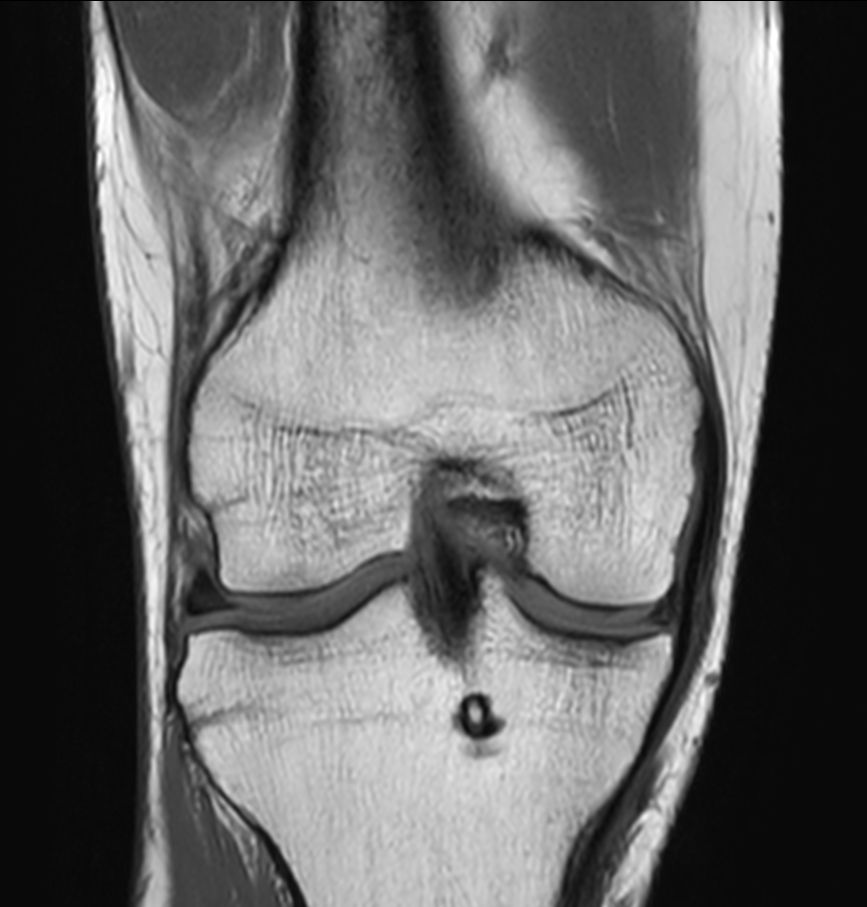

Coronal T1w TSECompressed SENSE